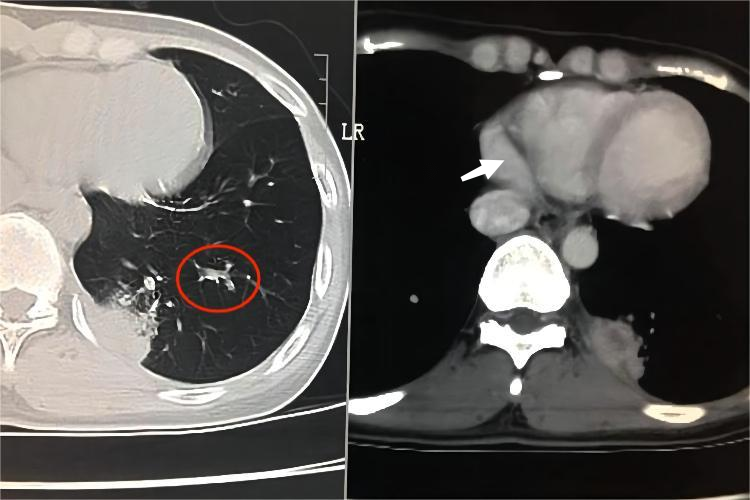

干酪性肺炎CT影像,主要显示为多发小空洞,增强CT显示多发坏死区,镜下有大片干酪样坏死灶,肺泡腔内有大量浆液纤维蛋白性渗出物。根据病灶范围的大小,可分为小叶性和大叶性干酪性肺炎,属于病情危重结核病之一,临床上常伴有低热、咳嗽等症状。